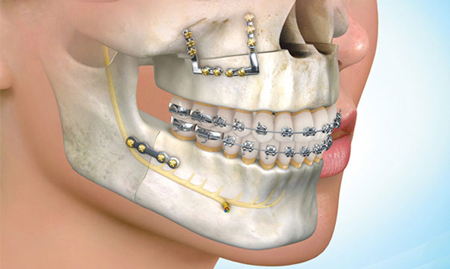

در صورتی که مشکلات فک با ارتودنسی قابل معالجه نباشد، جراحی فک میتواند مورد مناسبی برای بیمار باشد. در اکثر موارد، بیماران قبل و پس از جراحی و تا زمان بهبود و توازن کامل فک ها، از بریس های فانکشنال استفاده می کنند. متخصص ارتودنسی میتواند با جراح فک و صورت همکاری نموده و برنامه درمانی بیمار را معلوم کند.

جراحی فک بالا

بیمارانی که دارای فک بالای بیرون زده هستند یا نمایش لثه های آن ها در حالت لبخند بیش از مقدار عادی است.

درصورتی که به درمانهای ارتودنسی پاسخ ندهند کاندید جراحی فک میباشند. این جراحی سبب بهبود تعادل فک و دندان ها نسبت به لب بالا و بینی و چانه خواهد شد.

جراحی فک پائین

افرادی که دارای فک پائین بیش از حد بیرون زده یا بی اندازه عقب رفته هستتند می توانند تا حد زیادی با انجام جراحی فک از ظاهر و عملکرد مطلوب برخوردار شوند. بعلاوه در بیمارانی که دارای فک پائین نامساوی هستند هم جراحی فک تنها راه علاج این عدم تقارن و ایجاد تعادل در فرم صورت میباشد.